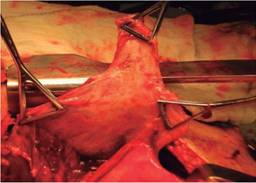

En la supuración pulmonar, más de la mitad fueron tratados con resecciones típicas; empleamos la lobectomía en el ASA I y II, evitando la resección atípica con sutura pulmonar para disminuir el riesgo de dehiscencia. La técnica de Monaldi o neumonostomía se realizó en ocho enfermos, cinco en ASA III y tres en IV; de ellos, cuatro por absceso de pulmón y cuatro por bullas infectadas (Cuadro II,Figuras 3 y 4).

Figura 4: Neumonectomía por absceso con tratamiento del bronquio con colgajo de músculo intercostal.